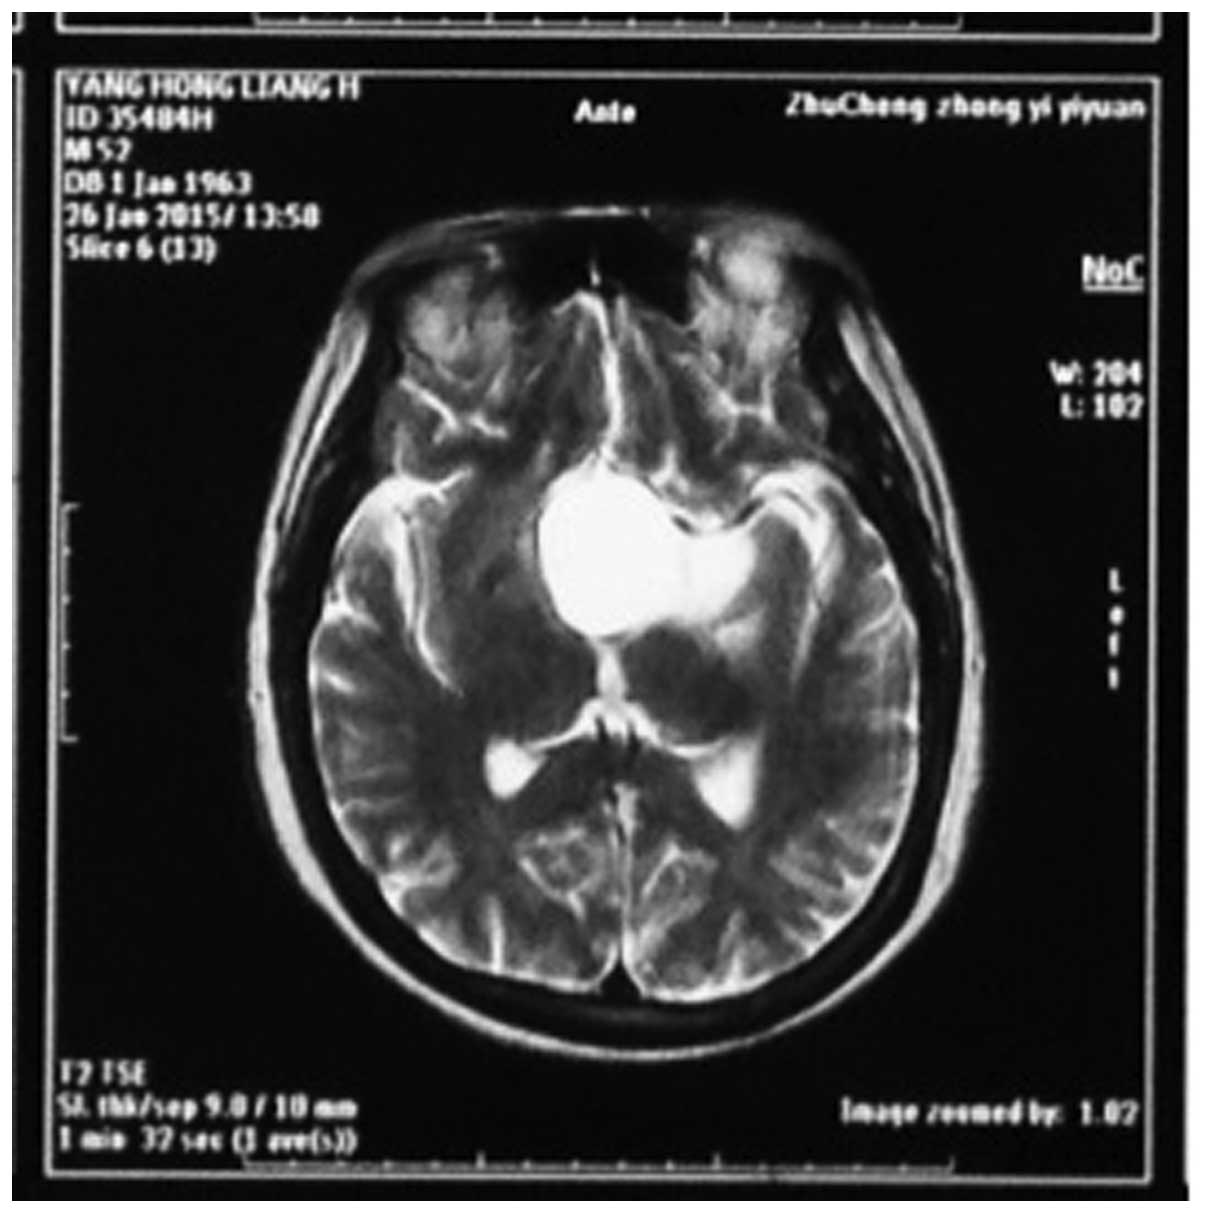

The MRI and CT investigations identified tumors in the sellar-hypothalamus region in 10 patients, sellar-anterior third ventricle in 5 patients, interior sellar-sellar region in 2 patients and brainstem in 3 patients. The tumors were cystic and solid in structure in 13 patients, cystic in 4 patients and solid in 3 patients (Figs. 1 and 2).

Figure 1.

Brain magnetic resonance imaging (MRI) showing long T2 signal in the saddle area in a 45-year-old man hospitalized due to headache and vision disorder.